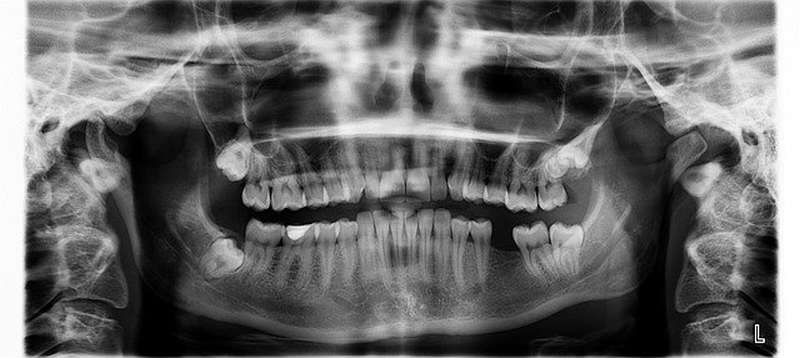

Ortopan boste potrebovali pri zobozdravniku za zobe, obzobno kost, nosno votlino in sinuse, da preveri, kakšno je stanje. Kakovosten ortopan je nenadomestljiv zato, da se vidi točno stanje in da zdravnik lahko dela varno. Ta slika se posname s posebno napravo in tako je že desetletja, ker niso izumili ničesar boljšega od tega. Na tej sliki se vidi, ali imate karies, tudi, če na zunaj ni viden. Vidi se tudi ali so nastale kakšne spremembe na kosteh in sinusih.

Ortopan je panoramsko slikanje zob in obraza in se ga najpogosteje uporablja. Slika je v 2D izvedbi, kjer se vidijo vsi vaši zobje in kosti ter tkiva. Na podlagi tega bo zobozdravnik dobro lahko oceni stanje zob in kosti ter tkiv. Ortopan je zelo pregledna slika, kjer se vidi tudi, kaj je z koreninami zob in če so kakšne težave z modrostnimi zobmi, ki se vraščajo v druge zobe ali čeljust. Vidi pa se tudi kostna struktura.